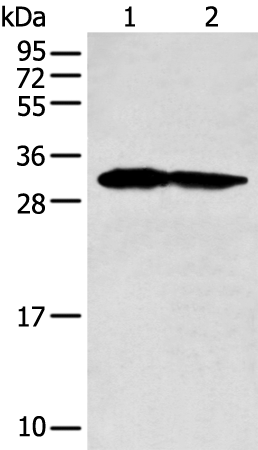

分类: 科研抗体货号: P06989别名: CPP32; SCA-1; CPP32B应用: WB,IHC反应种属: Human, Mouse, Rat

分类: 科研抗体货号: P06988别名: BCL2L4应用: WB,IHC反应种属: Human, Mouse, Rat